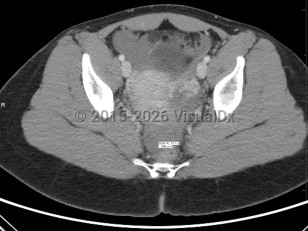

In the setting of hemodynamic stability with suspected ectopic pregnancy, provide:

- Emergent gynecologic consultation.

- Vascular access with 2 large bore peripheral intravenous (IV) lines.

- Fluid resuscitation with crystalloid, possible blood products.